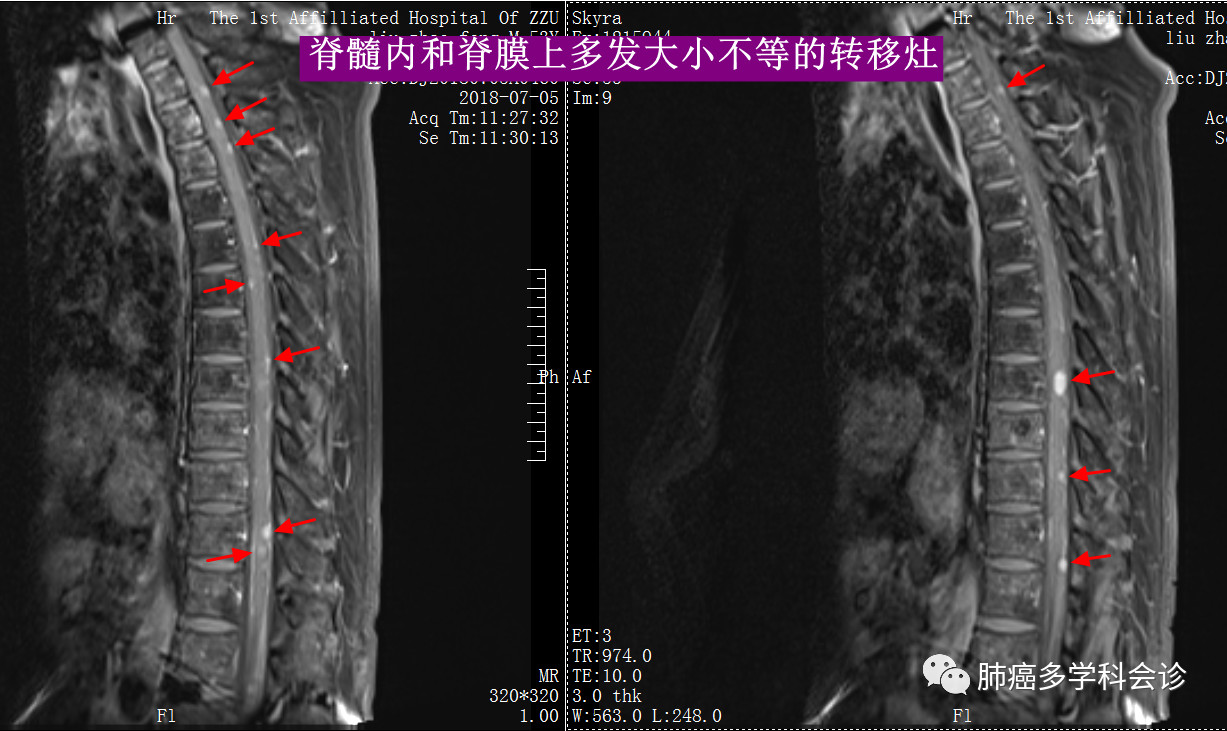

在脑部放疗结束后约8个月,患者自诉骶尾部疼痛、大便困难,曾怀疑是腰骶尾部椎骨转移,但做PET-CT并未发现异常。

随后做核磁共振检查,发现全脊髓脊膜多发转移,下图展示了全脊髓内的多发转移灶,转移灶表现为脊髓内的白色小点: